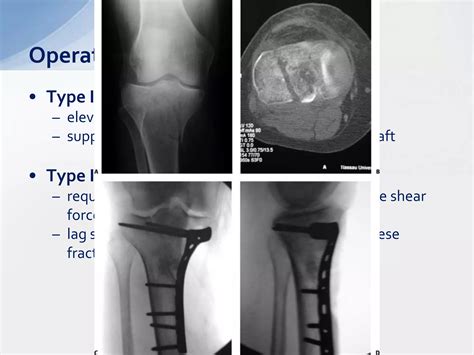

External fixators stabilize bone fractures externally on transparent ...